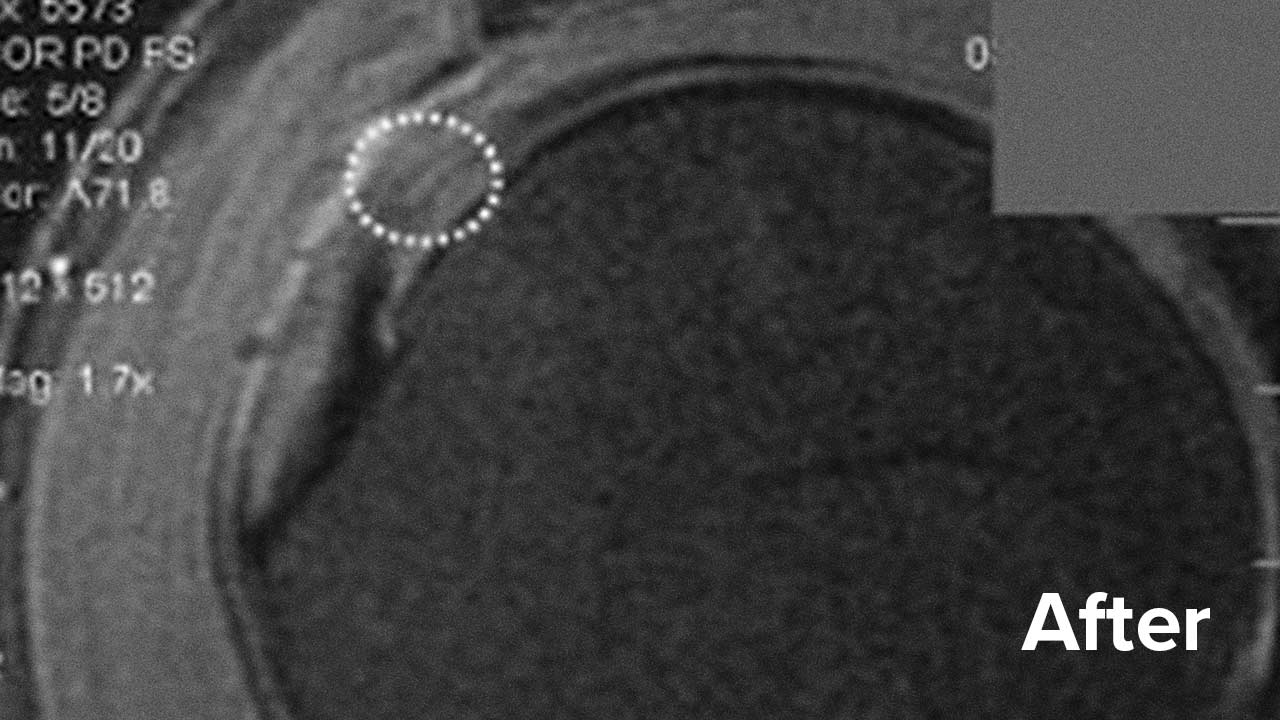

Take a look below at the outcomes of two of our patients who chose to have a Regenexx procedure for rotator cuff tear repair instead of surgery.

Scroll the arrow to the right to see the MRI of the rotator cuff before the treatment and to the left to see the outcome. The BEFORE shows a torn rotator cuff. The arrow points at a gap where the tendon should be. Once treated, the area will look like a dark band going diagonally, as seen on the AFTER.

Rotator cuff tear MRI – Patient 1